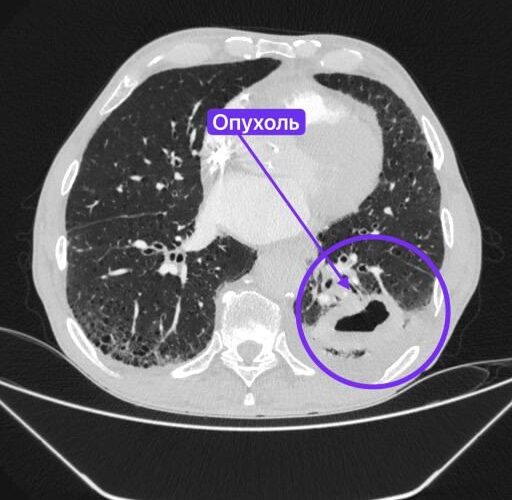

Медик направил мужчину в стационар, где он пролежал три недели. Врачи Нижнекамской ЦРМБ обследовали пациента и обнаружили образование, после чего рекомендовали взять направление к онкологу по месту жительства. Все это случилось под новогодние праздники. Поэтому к онкологу Вячеслав попал только в январе. Оказалось, что за это время в легком развился абсцесс, а на аорте образовалась аневризма.

Консилиумы в Набережных Челнах и Нижнекамске приняли решение, что мужчину невозможно оперировать в их условиях. В результате пациента направили в Казань. В РКБ его еще раз обследовали, взяли биопсию, чтобы определить характер опухоли.

Выяснилось, что у Вячеслава была злокачественная опухоль, которая начала разрушаться. В итоге через мини-разрез убрали образование, пораженные ткани и лимфоузлы. Операция прошла успешно. Пациент достаточно быстро пошел на поправку. Сейчас мужчина уже дома. Ему предстоит пройти курс химиотерапии.